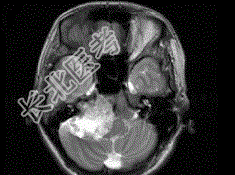

- 单项选择题女,45岁, 右耳听力下降半年余,CT检查如图, 最可能的诊断是